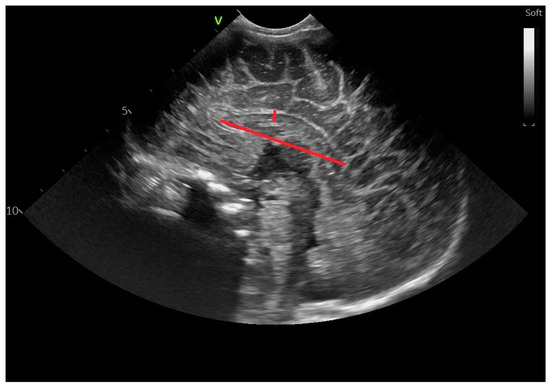

2.2. Head Ultrasound Measurements at TEA